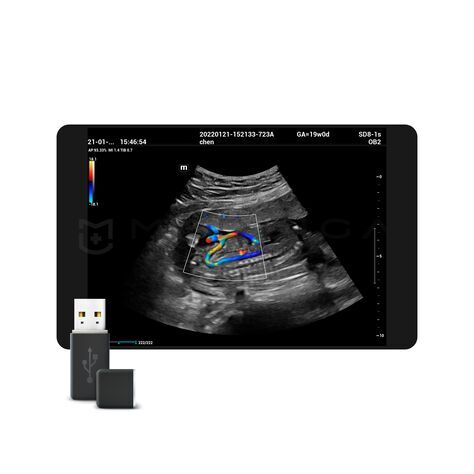

Области медицинского применения в основном определяются типом датчиков, работающих с ультразвуковым прибором и наличием специализированных режимов работы.

УЗИ аппараты общей визуализации предназначены для широкого спектра исследований, оперативной диагностики и повсеместно применяются в кабинетах ультразвуковой диагностики.